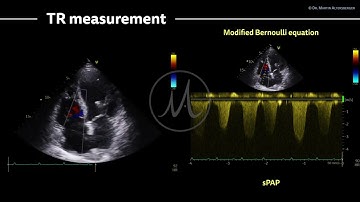

How to estimate RVSp using TR jet?